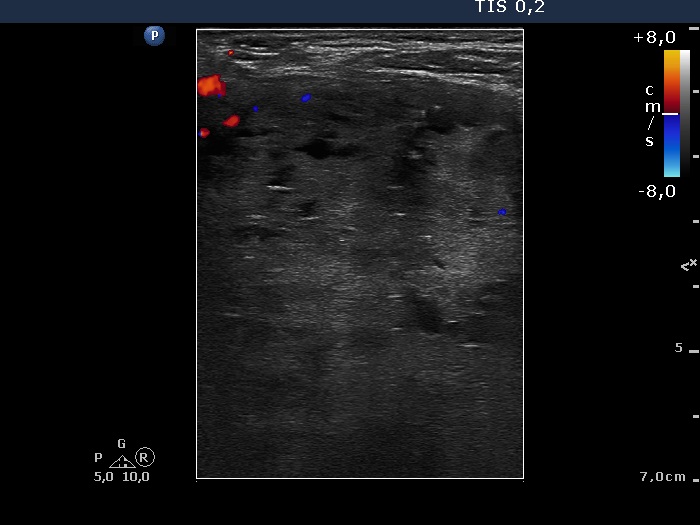

Benign nodular hyperplasia - Case 49. (ultrasonographic picture 6)

Left lobe, longitudinal scan, color Doppler mode. Note the lack of type perinodular blood flow.